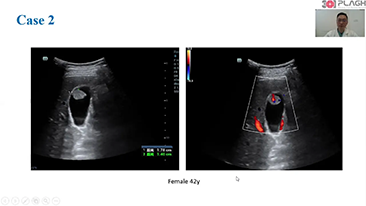

Menos preocupa??o com o estetoscĂłpio e mais com o ultrassom?

? necessĂĄrio otimizar fluxos de trabalho de obstetrĂcia e ginecologia para suportar grandes volumes na triagem da saĂșde da mulher. Por exemplo, as mĂĄs-forma??es do sistema nervoso central (SNC) s?o uma das anomalias congĂȘnitas mais comuns. Obten??o de imagens ruins devido Ă mĂĄ posi??o fetal, o MSP Ă© particularmente difĂcil de ser encontrado em um ultrassom 2D. Portanto, a detec??o e as medi??es automĂĄticas podem aumentar muito a eficiĂȘncia da realiza??o do exame.